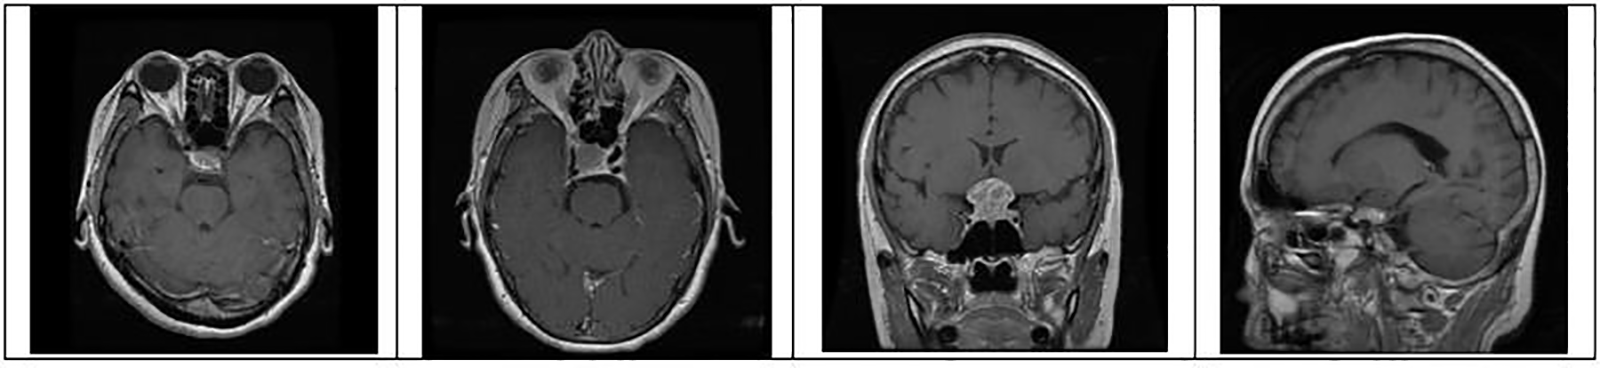

where pc is a package configuration of brain tumor algorithm, mf is making the file of brain tumor, and m is brain tumor contour make. Figs. 4 to 6 represent three different types of brain tumors: glioma, meningioma, and pituitary. With algorithm 1, all said types were identified. The output of different kinds of brain tumor detection and its sample is represented in Figs. 4 to 6. Here glioma is a low-grade tumor, like a normal brain, with a similar texture and colour. Here intra-operative sampling and the enhanced visual tumor have been applied as glioma detection steps, as shown in Fig. 4. For meningioma detection, vision change, seizures, and confusion were checked with dura mater and pia mater, as shown in Fig. 5. Here DeepMedic architecture with t1 method for MRI image. The same further process is applied to pituitary tumors. The EDLA architecture process was applied, and results were generated.

Figure 6: Identification of brain tumor-type pituitary samples from the dataset for training and testing